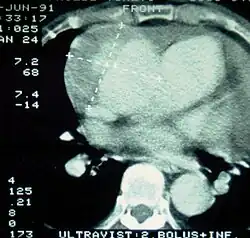

| Computertomografie (CT) | Legende |

| Aortendissektion Typ Stanford A 1 Aorta ascendens, wahres Lumen – 2 falsches Lumen – 3 Lungenschlagader 4 Aorta descendens – 5 Brustwirbelkörper | |

Eine mit Kontrastmittel durchgeführte CT gestattet eine umfassende und exakte Darstellung der gesamten Aorta und kann sowohl die Dissektion selbst als auch deren räumliche Beziehung zu den Seitenästen der Aorta und eventuelle Blutungen in der Umgebung zuverlässig darstellen. Eine mögliche Beteiligung der Aortenklappe ist allerdings nicht erkennbar, die klappennahen Aortenabschnitte sind auf Grund von Artefakten durch das schlagende Herz bei älteren CT-Geräten schwieriger zu beurteilen. Mit diesen Geräten wurde in mehreren Studien eine Sensitivität von 83–94 % und eine Spezifität von 87–100 % ermittelt, moderne Spiral-CT erreichen eine Sensitivität von durchschnittlich mehr als 95 %.